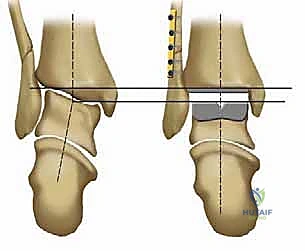

يتكون مفصل الكاحل الأساسي (المفصل الظنبوبي الكاحلي - Tibiotalar joint) من التقاء ثلاث عظام رئيسية:

1. عظمة الظنبوب (Tibia): وهي عظمة الساق الكبرى، وتشكل السقف والجزء الداخلي من الكاحل (الكعب الداخلي - Medial Malleolus).

2. عظمة الشظية (Fibula): وهي عظمة الساق الصغرى، وتشكل الجزء الخارجي من الكاحل (الكعب الخارجي - Lateral Malleolus).

3. عظمة الكاحل (Talus): وهي العظمة السفلية التي تستقر داخل التجويف الذي تشكله عظمتا الساق، وتعمل كنقطة ارتكاز محورية للقدم.

* التصميم الميكانيكي: يشارك هذا النظام نفس الهندسة التشريحية الممتازة للمكونات المعدنية لنظام سالتو، ولكن مع اختلاف جوهري واحد: المكون البلاستيكي (البولي إيثيلين) هنا ثابت (Fixed-bearing) ويتم قفله بإحكام داخل المكون المعدني العلوي (الظنبوبي).

* الفلسفة وراء التصميم: أثبتت الأبحاث وخبرة الجراحين، بما في ذلك الأستاذ الدكتور محمد هطيف، أنه إذا تم إجراء القصات العظمية أثناء الجراحة بدقة متناهية تتوافق مع التشريح الطبيعي، فإن الحاجة إلى حركة واسعة للمكون البلاستيكي تقل بشكل كبير.